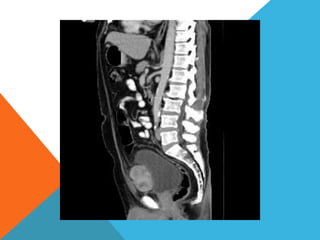

El paciente presentó síntomas de sangrado digestivo y pérdida de peso. Exámenes revelaron gastritis crónica asociada a H. pylori. Un tumor fue descubierto en una colonoscopia normal. La cirugía removió un tumor fibroide solitario, una rara neoplasia mesenquimal que usualmente crece lento y tiene bajo potencial de malignidad. El pronóstico después de la remoción quirúrgica es generalmente bueno.